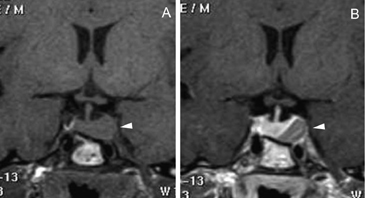

Figura 1A y B. TAC con contraste yodado, corte coronal, muestra un microadenoma lateralizado a izquierda (punta de flecha). Control a los 2 años. TAC con contraste yodado, corte coronal, demuestra aumento de volumen del microadenoma, lo que es infrecuente de observar en clínica (punta de flecha).

En los microadenomas el crecimiento tumoral es observado en una minoría de los casos (Figuras 1A y 1B), en contraste con los macroadenomas, los cuales cuando son encontrados en forma accidental (incidentalomas pituitarios) han demostrado un aumento de tamaño que varía entre 25 a 50%27-31.